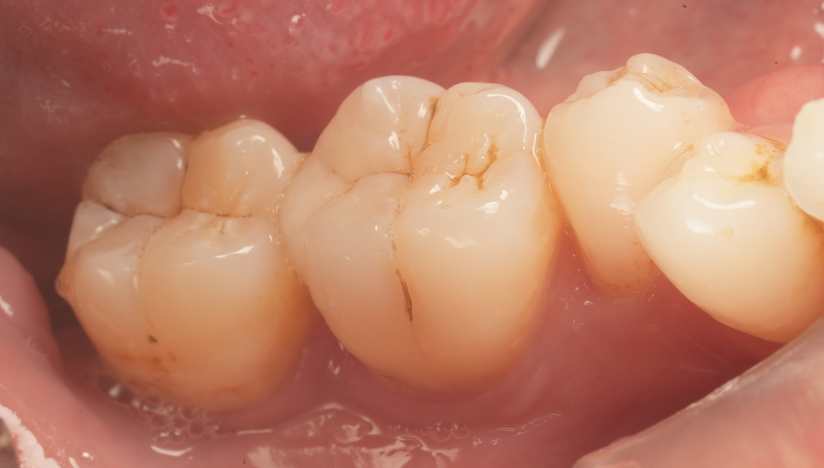

MIを意識しながら予防的拡大を行い

虫歯治療を完了させた症例

タップで写真の拡大ができます。

Before

After

主訴

虫歯の治療をしたい。

治療内容

セラミックアンレー2本

セラミックインレー1本

IDS(Immadiate Dentin Sealing)3本

治療期間

通院回数2回

治療費用

390,500

治療の

リスク

術後に一時的な知覚過敏症状が出る可能性があります。